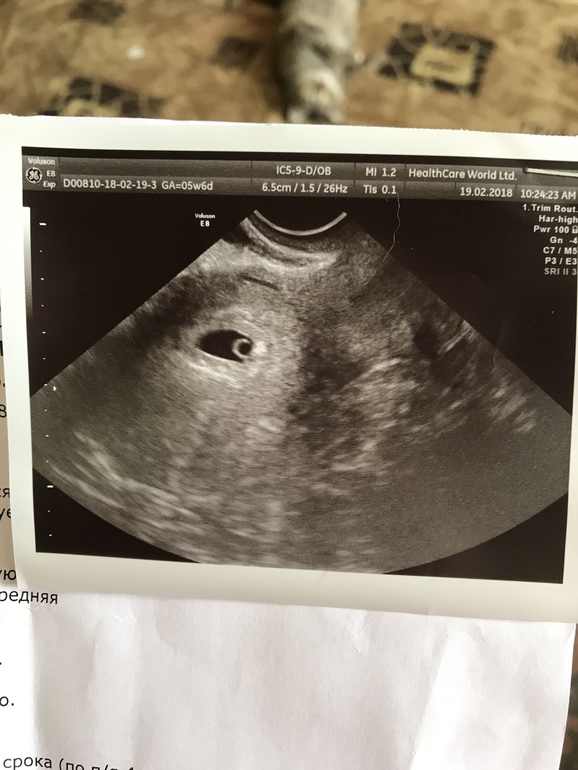

УЗИ на 14дз

Девочки, всем привет. Сходила я сегодня на УЗИ, по мес срок 6 недель, на УЗИ поставили мне срок 4-5, сказали, что всё отлично, всё по нормам, но эмбрион пока не определяется. Я заволновалась, но она успокоила меня тем, что кровоток есть отличный, значит и эмбрион есть, но просто ещё рано. Я теперь вся на нервах!! Может действительно ещё рано? А может это проблема??